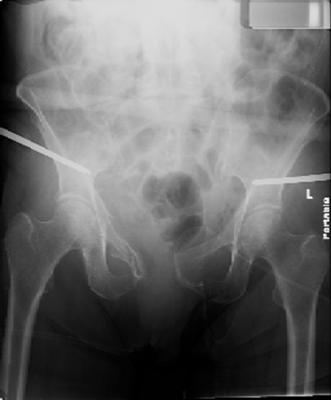

so the question is what next operatively if anything? concerns are infection, nonunion anteriorly and possible incompetence of the pelvic floor which may lead to prolapse issues. right rami are comminuted and plating may entail ilioinguinal approach to extend plate laterally to right iliac wing. retrograde screw up right rami is an option but I am not convinced it will add much. adding SI screws very doable, but major concern is restoring anterior ring. so far wound is clean and closed over a drain, and I have no plans to open it back up and wash again.

maintaining pelvic alignment in ex-fix in 70 yo female for any length of time may be challenging.

any thoughts? would anyone plate the pubic symphysis to close the gap and leave the more lateral rami fractures alone? the most recent pelvic case on this website involved pts with suprapubic catheters and antibiotic options including resorbable beads. I wonder how many people would plate and place antibiotic beads. thanks.